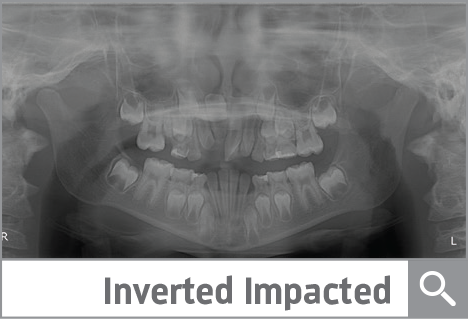

Inverted Impacted Tooth— Patience Is a Virtue

This great before-and-after case involves a 9-year-old boy who came in with two impacted incisors, an oddly inverted #8 and a slew of other challenges. Check out the full treatment.